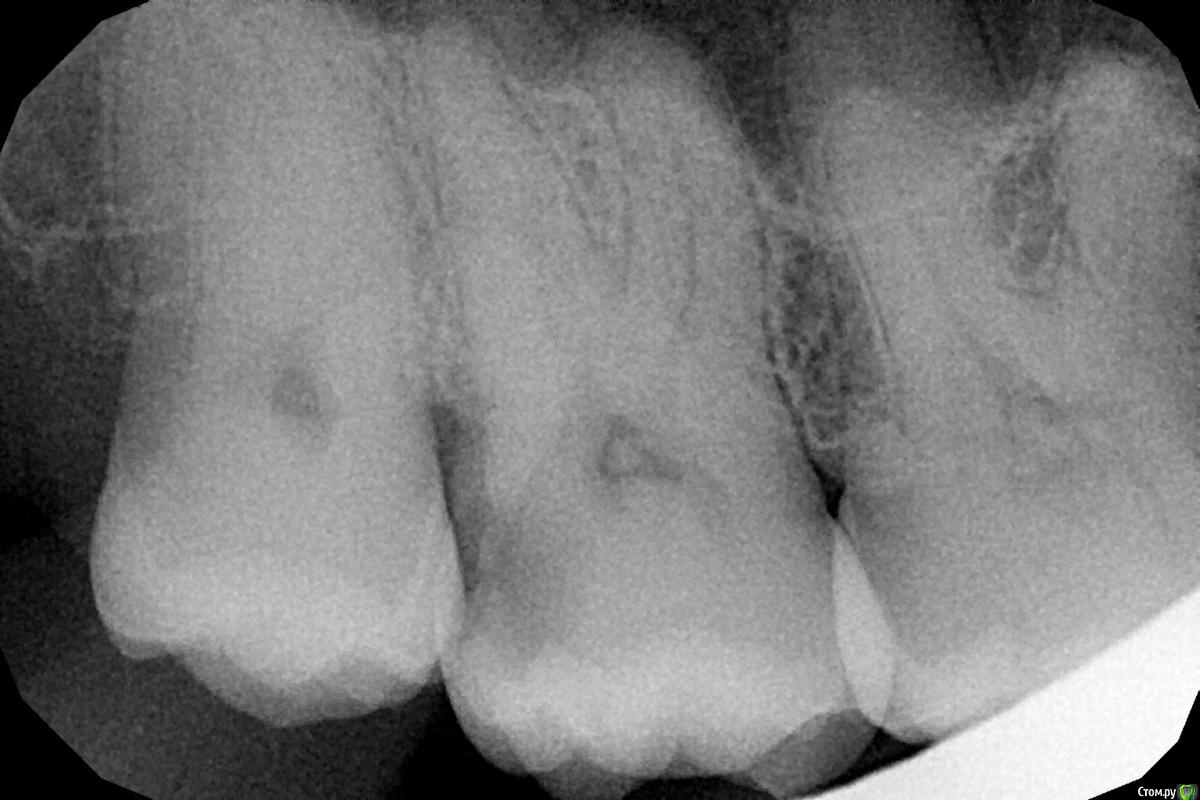

legoz1 Опубликовано 9 апреля, 2017 Поделиться Опубликовано 9 апреля, 2017 Здравствуйте. Болела подолгу десна после еды, сделал снимок. Предложили сверлить каналы и ставить пломбу за очень приличную сумму, но я ничего ужасающего на снимке не вижу. После чистки от камня десна беспокоит, но значительно меньше. Подскажите, есть ли здесь действительно зуб, требующий капремонта? Спасибо. Ссылка на комментарий

Stomart Опубликовано 9 апреля, 2017 Поделиться Опубликовано 9 апреля, 2017 Зуб по центру требует капремонта срочного. Ссылка на комментарий

red_butler Опубликовано 9 апреля, 2017 Поделиться Опубликовано 9 апреля, 2017 Седьмой лечить, восьмой удалить. Ссылка на комментарий

red_butler Опубликовано 10 апреля, 2017 Поделиться Опубликовано 10 апреля, 2017 С 7-м понятно, а зачем 8-й удалять?Он создает проблемы с осуществлением индивидуальной гигиеной и по сути явился причиной кариеса. Ссылка на комментарий

St. Опубликовано 20 апреля, 2017 Поделиться Опубликовано 20 апреля, 2017 Разрушение зуба близко к десне. Скорее всего после чистки и пасты для десен воспаление десны там уменьшилось, поэтому и не беспокоит.Но проблема с зубом все равно осталась и чем больше затягивать, тем больше вероятность что он начнет болеть. Тогда придется 100% "уборать нерв", и искать стоматолога как припечет после бессонной ночи с зубной болью. 1 Ссылка на комментарий

legoz1 Опубликовано 21 апреля, 2017 Автор Поделиться Опубликовано 21 апреля, 2017 (изменено) После вскрытия полости, врачом было принято решение наложить на пораженный участок фторсодержащий состав и установить пломбу - нервы не удалять. При возникновении болей - депульпация, без вариантов. Благодарю всех за помощь! Изменено 21 апреля, 2017 пользователем legoz1 Ссылка на комментарий